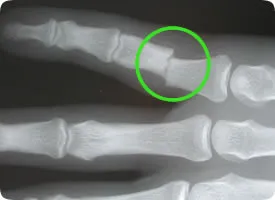

- Röntgenonderzoek: Om de diagnose te bevestigen, wordt een röntgenfoto (RX) van de hand of vinger gemaakt. Op de foto is te zien welk vingerkootje gebroken is en of de delen verplaatst zijn. Aan de hand van de RX wordt beoordeeld of de breuk stabiel is. Een stabiele vingerfractuur betekent dat de botstukken niet of nauwelijks verschoven zijn; een instabiele fractuur betekent dat het bot misstaat of kan verschuiven bij beweging. Bij meervoudige breuken of onduidelijke breuklijnen kan eventueel een CT-scan extra informatie geven, maar dit is zelden nodig.